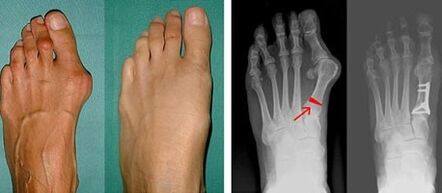

Pirmojo kojos piršto Valgus deformacija dažniausiai pažeidžia brandaus amžiaus moteris, tačiau ja serga ir vyrai. Deformuotas nykščio pagrindas neatrodo estetiškai. Tokiu atveju žmogus jaučia fizinį diskomfortą, o pažengusioje stadijoje – skausmą. Didžiojo piršto nukrypimas yra netolygios kūno apkrovos pėdai pasekmė. Tokie pokyčiai neigiamai veikia pėdas ir kitus pirštus.

Pirmajame didžiojo ir mažojo piršto valgus nustatymo etape gydytojas atlieka vizualinį tyrimą. Tokiu būdu jis nustato patologijos vystymosi stadiją. Norint nustatyti detalius sąnarių pokyčius, skiriami rentgeno spinduliai ir plantografija.

Jei vizualinis tyrimas ir rentgeno spinduliai neduoda jokio rezultato, pacientas siunčiamas plantografijai, kad būtų nustatytas galimas plokščias pėdas. Šis metodas apima pėdų atspaudus, kurių pagrindu pacientui gaminami ortopedinių savybių turintys batai ar vidpadžiai. Tada pacientui skiriama podometrija. Šis metodas naudoja kompiuterinę analizę, leidžiančią nustatyti žmogaus svorio spaudimą pėdoms. Išplėstinės diagnostikos rezultatai yra pagrindas renkantis pirmojo ir antrojo piršto išlinkimo gydymo metodą.